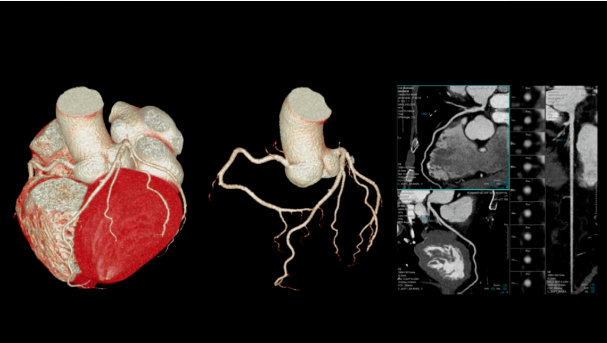

3、冠状动脉CTA :

可以在短短数秒时间内快速且无创的诊断冠脉狭窄、斑块等疾病,对于诊疗急性心梗等疾病具有重要意义。